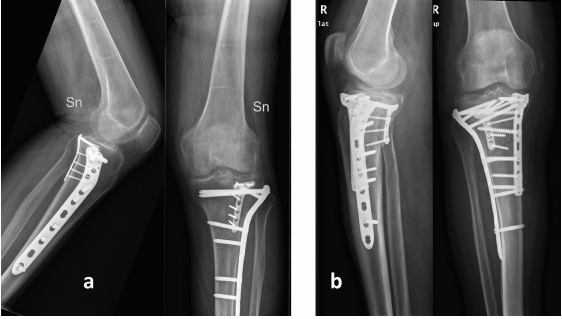

a 一名79岁男性的膝关节前后位(AP)和侧位X线片,他患有双柱(3型)TP骨折,术后5个月随访,显示最终结果以及外侧和后侧钢板的位置。b. 一名71岁男性的膝关节前后位(AP)和侧位X线片,他患有三柱(4型)TP骨折,术后1个月随访,显示最终结果以及内侧、外侧和后侧钢板的位置。